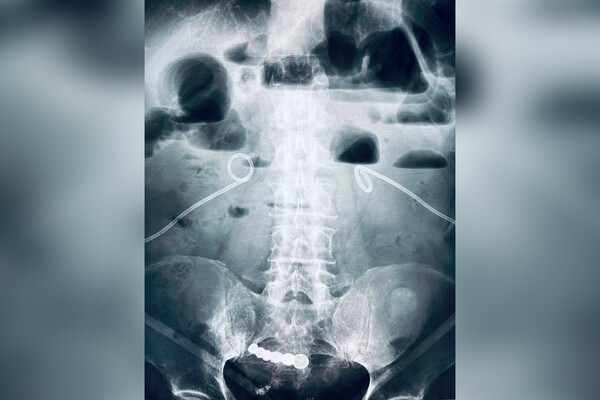

Пенсионер из Кемеровской области шесть лет прожил со вставной челюстью в кишечнике, мужчина случайно проглотил инородный предмет и не обращался к врачам. Об этом сообщил глава регионального Минздрава Дмитрий Беглов на странице во «ВКонтакте».

Пожилой мужчина обратился в городскую больницу Кемерова с жалобами на острою боль в области живота. В ходе обследования медики обнаружили в кишечнике пенсионера зубной протез, пациент рассказал врачам, что шесть лет назад случайно проглотил вставную челюсть.

Инородное тело не доставляло неудобств, и мужчина решил не обращаться к врачам. Вставную челюсть удалили малоинвазивным методом. Пенсионер выписан на амбулаторное лечение.